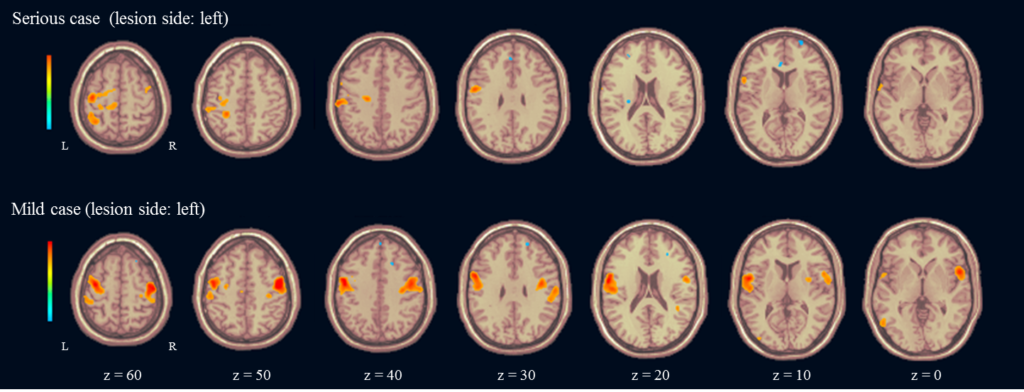

また,一般の病院で頻用されている1.5 Tesla MRIを用いた我々の研究(Tamari, 2018)においても,運動機能の障害が軽度な脳卒中患者は健常人に類似したconnectivityを示し,運動機能の障害が重度な患者はconnectivityが減弱していました(Figure 2).